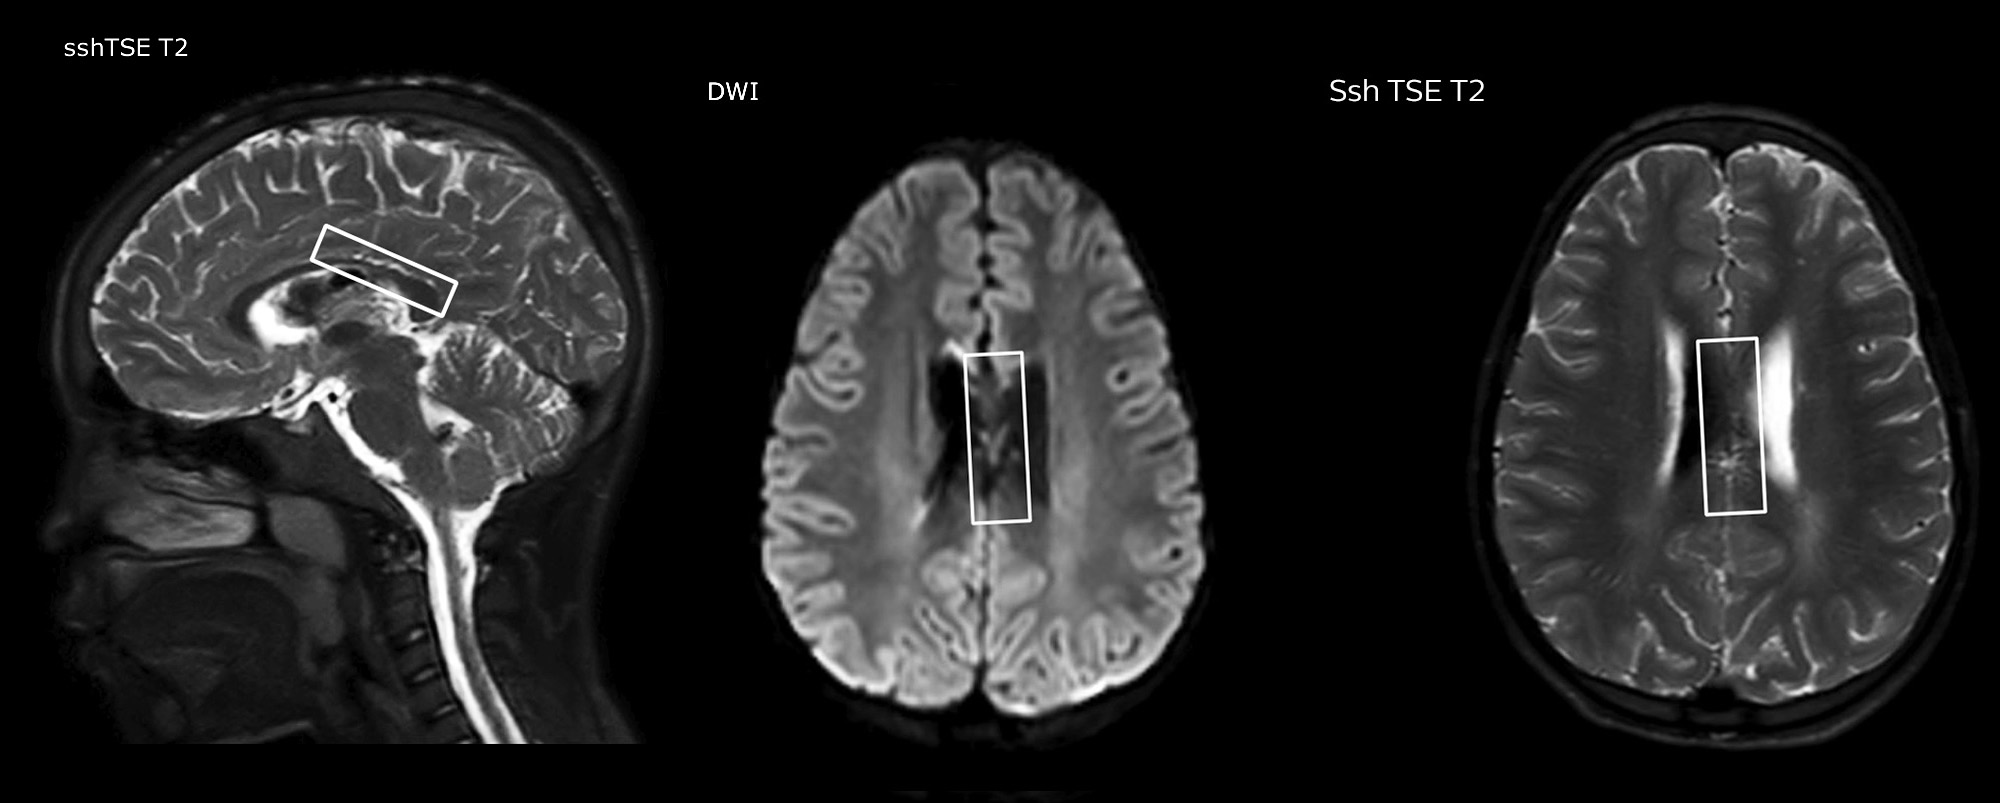

Philips mDIXON TSE ist ein Zweipunkt-DIXON-Verfahren, das Wasser- und Fettsignale trennt und so eine zeiteffiziente, fettfreie Bildgebung auch bei komplexen neurologischen Anatomien ermöglicht. „mDIXON TSE ist eine der signifikantesten Verbesserungen bei Bildgebungssequenzen, die wir am PCH bisher realisiert haben“, sagt Dr. Miller. „Dank der multiparametrischen Erfassung können wir Bilder mit Fettsuppression und entsprechende T2-Bilder ohne Fettsuppression in derselben Sequenz aufnehmen. Außerdem war es bei den bisherigen Methoden möglich, dass diese durch Artefakte aufgrund einer ungünstigen Patientenanatomie oder durch Bedienfehler beeinträchtigt wurden. Mit mDIXON verfügen wir jetzt jedoch über eine robuste und zuverlässige Methode zur Fettsuppression.“ Historisch gesehen bereitet die Fettsuppression am Ende des Sichtfeldes Schwierigkeiten, insbesondere bei der Bildgebung der gesamten Wirbelsäule und bei diffizilen Patientenanatomien wie dem unteren Halsbereich. „Aufgrund der einzigartigen Fettsuppressionseigenschaften von mDIXON treffen diese Probleme jedoch nicht mehr zu“, erläutert Dr. Miller. „Wir erhalten routinemäßig eine homogene Fettsuppression unter praktisch allen Bedingungen. Darüber hinaus konnten wir auch die Effizienz steigern, weil wir keine Sequenzen mehr aufgrund solcher technischen Einschränkungen wiederholen müssen.“

„mDIXON TSE hat unsere Diagnosesicherheit erhöht, weil Abweichungen, bei denen die Fettsuppression für die Diagnose entscheidend ist, definitiv abgeklärt werden können, zum Beispiel metastatische Erkrankungen oder ossale Veränderungen.“

„mDIXON TSE erweist sich bei Patienten mit Läsionen oder pathologischen Befunden im Weichteilgewebe wie Gesicht und Hals am nützlichsten sowie bei Patienten mit kontrastverstärkenden Abweichungen, die mit Fettsuppression am besten sichtbar sind“, so Dr. Miller weiter. „Unsere gesamte Wirbelsäulenbildgebung enthält mittlerweile mDIXON T2-Bilder auf reiner Wasserbasis, und dies ermöglicht uns die Erkennung von Pathologien, die bei einer Bildgebung ohne Fettsuppression zum Beispiel von Knochenverletzungen nicht sichtbar wären. Außerdem ist es nicht nötig, weitere TSE-T2-Standardbilder aufzunehmen, weil die mDIXON In-Phase-Bilder gleichwertig mit TSE-T2-Standardbildern sind.“